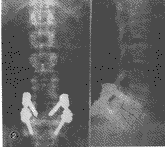

本组23例患者获得随诊,随诊时间6个月~5年8月,平均3年6个月,术后症状基本消失,有2例术后L5神经根有刺激症状,经治疗2~6周消失。随访时常规拍摄腰椎正侧位及双斜位X线片,随诊患者均在4个月后达到骨性愈合,滑脱复位率为80%~100%(图2)。无固定螺钉松动、拔出、断裂及脊椎再滑脱现象。

图2 患者,男,39岁,术前X线片示L5滑脱Ⅱ度(①),术后完全复位(②)